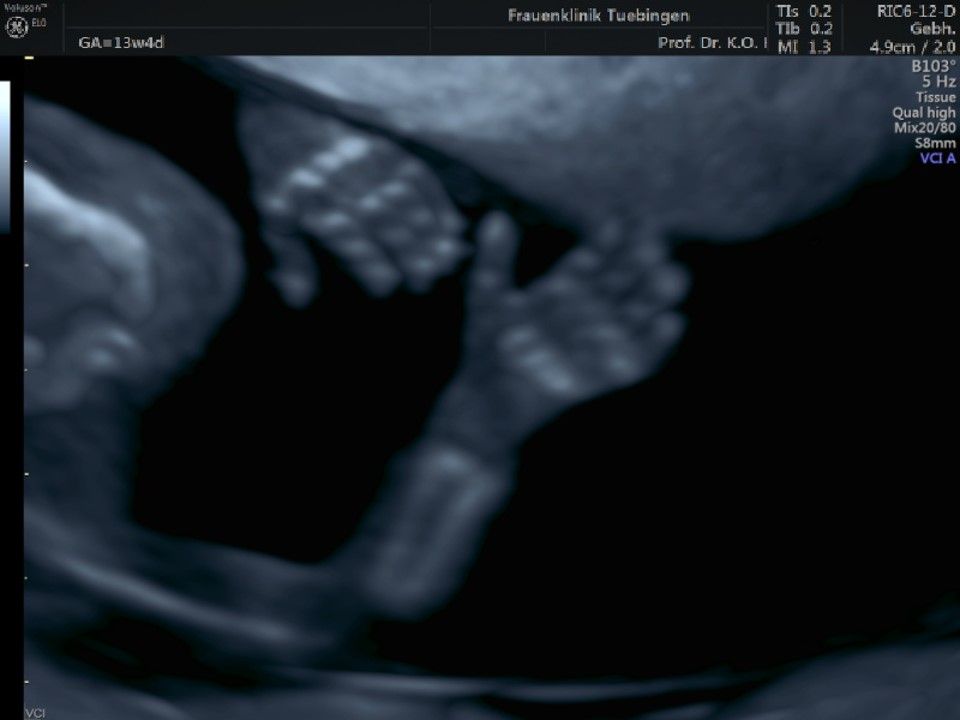

Im Rahmen des Ersttrimester-Screenings untersuchen wir die Organe des Feten mittels Ultraschall. Dabei machen wir auch gerne ein Bild für Sie.

Obwohl der Fet zu diesem Zeitpunkt erst zwischen 5 und 8cm groß ist, lassen sich bereits etwa die Hälfte aller schwerwiegenden Fehlbildungen erkennen bzw. ausschließen. Sollten wir eine Auffälligkeit sehen, werden wir mit Ihnen den Befund und das weitere Vorgehen ausführlich besprechen.

Fetale Anatomie